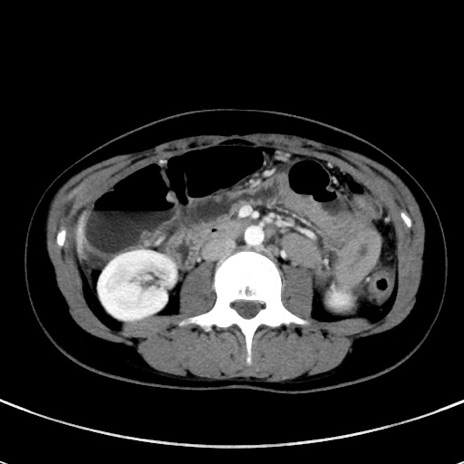

症例17(横断像)

【症例】20歳代女性

【主訴】嘔吐、下腹部痛

【現病歴】昨日夕食後に嘔吐し下腹部痛が出現。本日になっても嘔吐持続し改善しないため来院。

【身体所見】意識清明、BT 37.2℃、BP 108/67mmHg、腹部:平坦、やや硬、下腹部正中から右にかけて圧痛あり、反跳痛軽度あり、tapping pain(+)。

【データ】WBC 13600、CRP 14.94